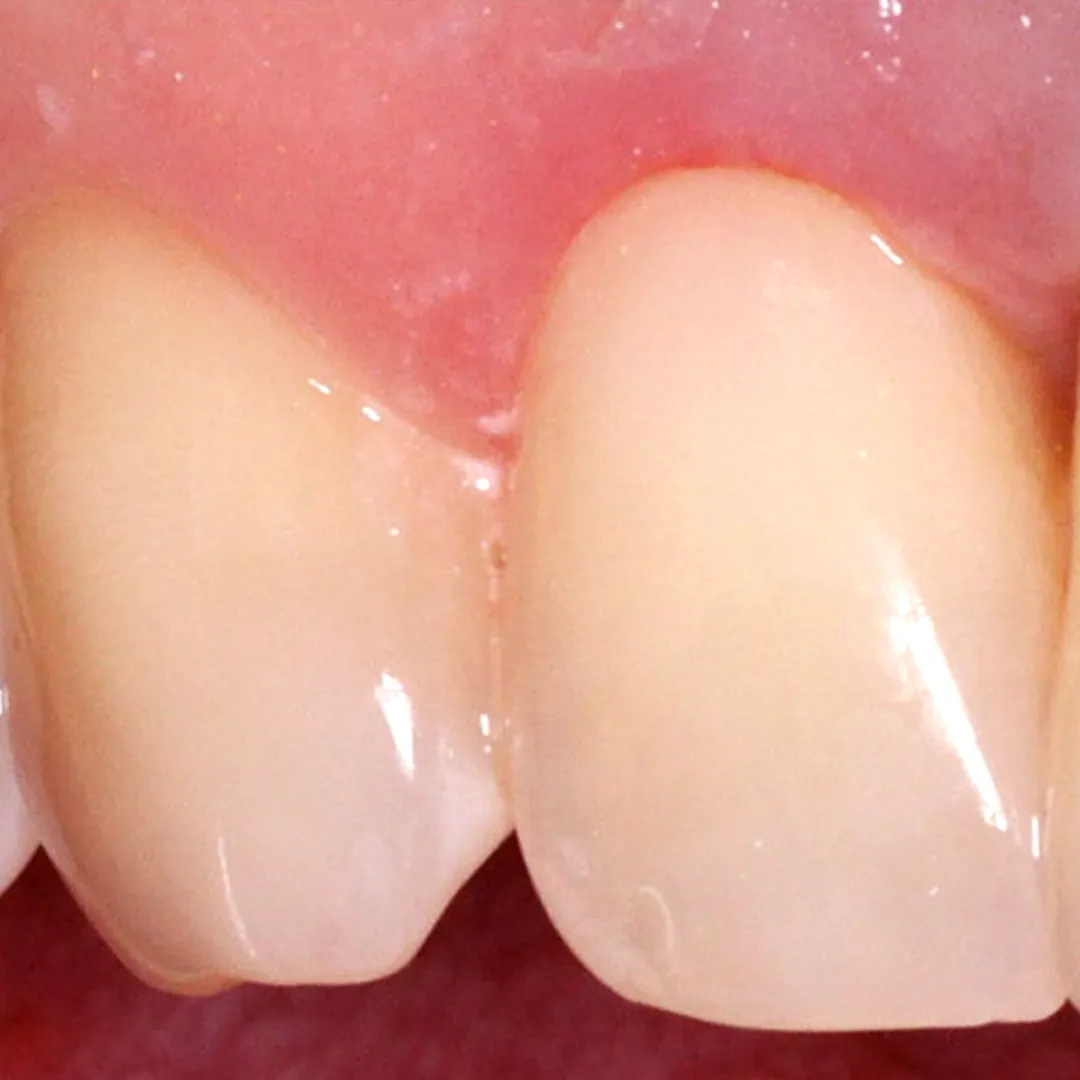

До и после лечения

Пациент обратился с жалобой на эстетический недостаток в области нижнего зуба справа. После обработки кариозной полости врач выявил глубокий кариес. Дно и стенки полости плотные, гладкие, блестящие, при зондировании крепетируют. Реакция на холод слабоболезненна, на перкуссию — безболезненна. Диагноз — хронический глубокий кариес.

- пломбирование Vitremer (A3);

- микроконтурирование и макроконтурирование пломбы.